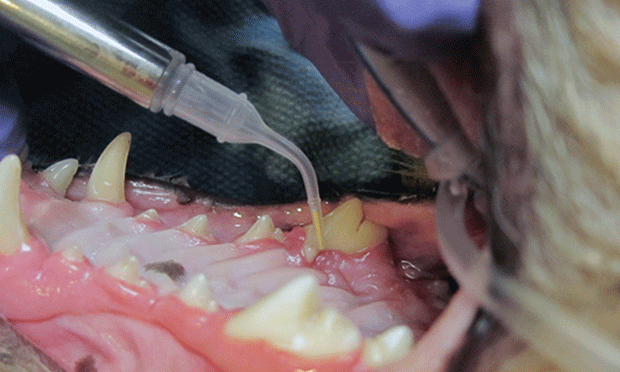

How Local Antimicrobials Can Help Manage Periodontal Disease

What are the warning signs of periodontal disease